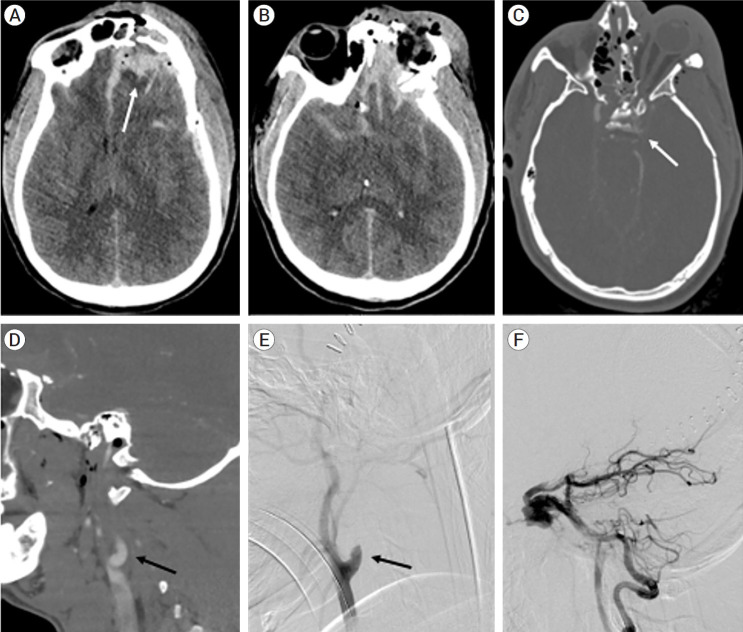

我们报告了一例 24 岁患者的病例,他在头部外伤后出现左侧颈内动脉外伤性闭塞。他接受了诊断性脑血管造影,发现左侧颈内动脉-海绵状静脉瘘(CCF)直接从后循环穿过后交通动脉逆行充盈。由于左侧颈内动脉(ICA)严重受损,无法进行ICA重建修复。患者采用后方逆行入路,通过线圈栓塞对CCF进行了解构修复。线圈被成功置入海绵窦并返回左侧 ICA,CCF 被完全治愈,治疗后的 CCF 远端恢复了脑灌注。我们回顾了CCF的类型、临床表现及其血管内治疗方法。文献中很少报道逆行进入直接CCF的方法,我们认为这种方法为经过适当选择的患者提供了一种可行的替代方案。

We report a case of a 24-year-old patient who presented after a head trauma with a traumatic occlusion of his left internal carotid artery. He underwent diagnostic cerebral angiogram and was found to have a direct left carotid-cavernous fistula (CCF) with retrograde filling from the posterior circulation across the posterior communicating artery. Because of the severe injury to the left internal carotid artery (ICA), reconstructive repair of the ICA was not possible. The patient underwent deconstructive repair of the CCF by coil embolization using a posterior retrograde approach. Coils were successfully placed in the cavernous sinus and back into the left ICA with complete cure of the CCF and restoration of cerebral perfusion distal to the treated CCF. We review the types of CCFs, their clinical presentation, and their endovascular treatments. Retrograde access of a direct CCF is rarely reported in the literature, and we believe this approach offers a viable alternative in appropriately selected patients.